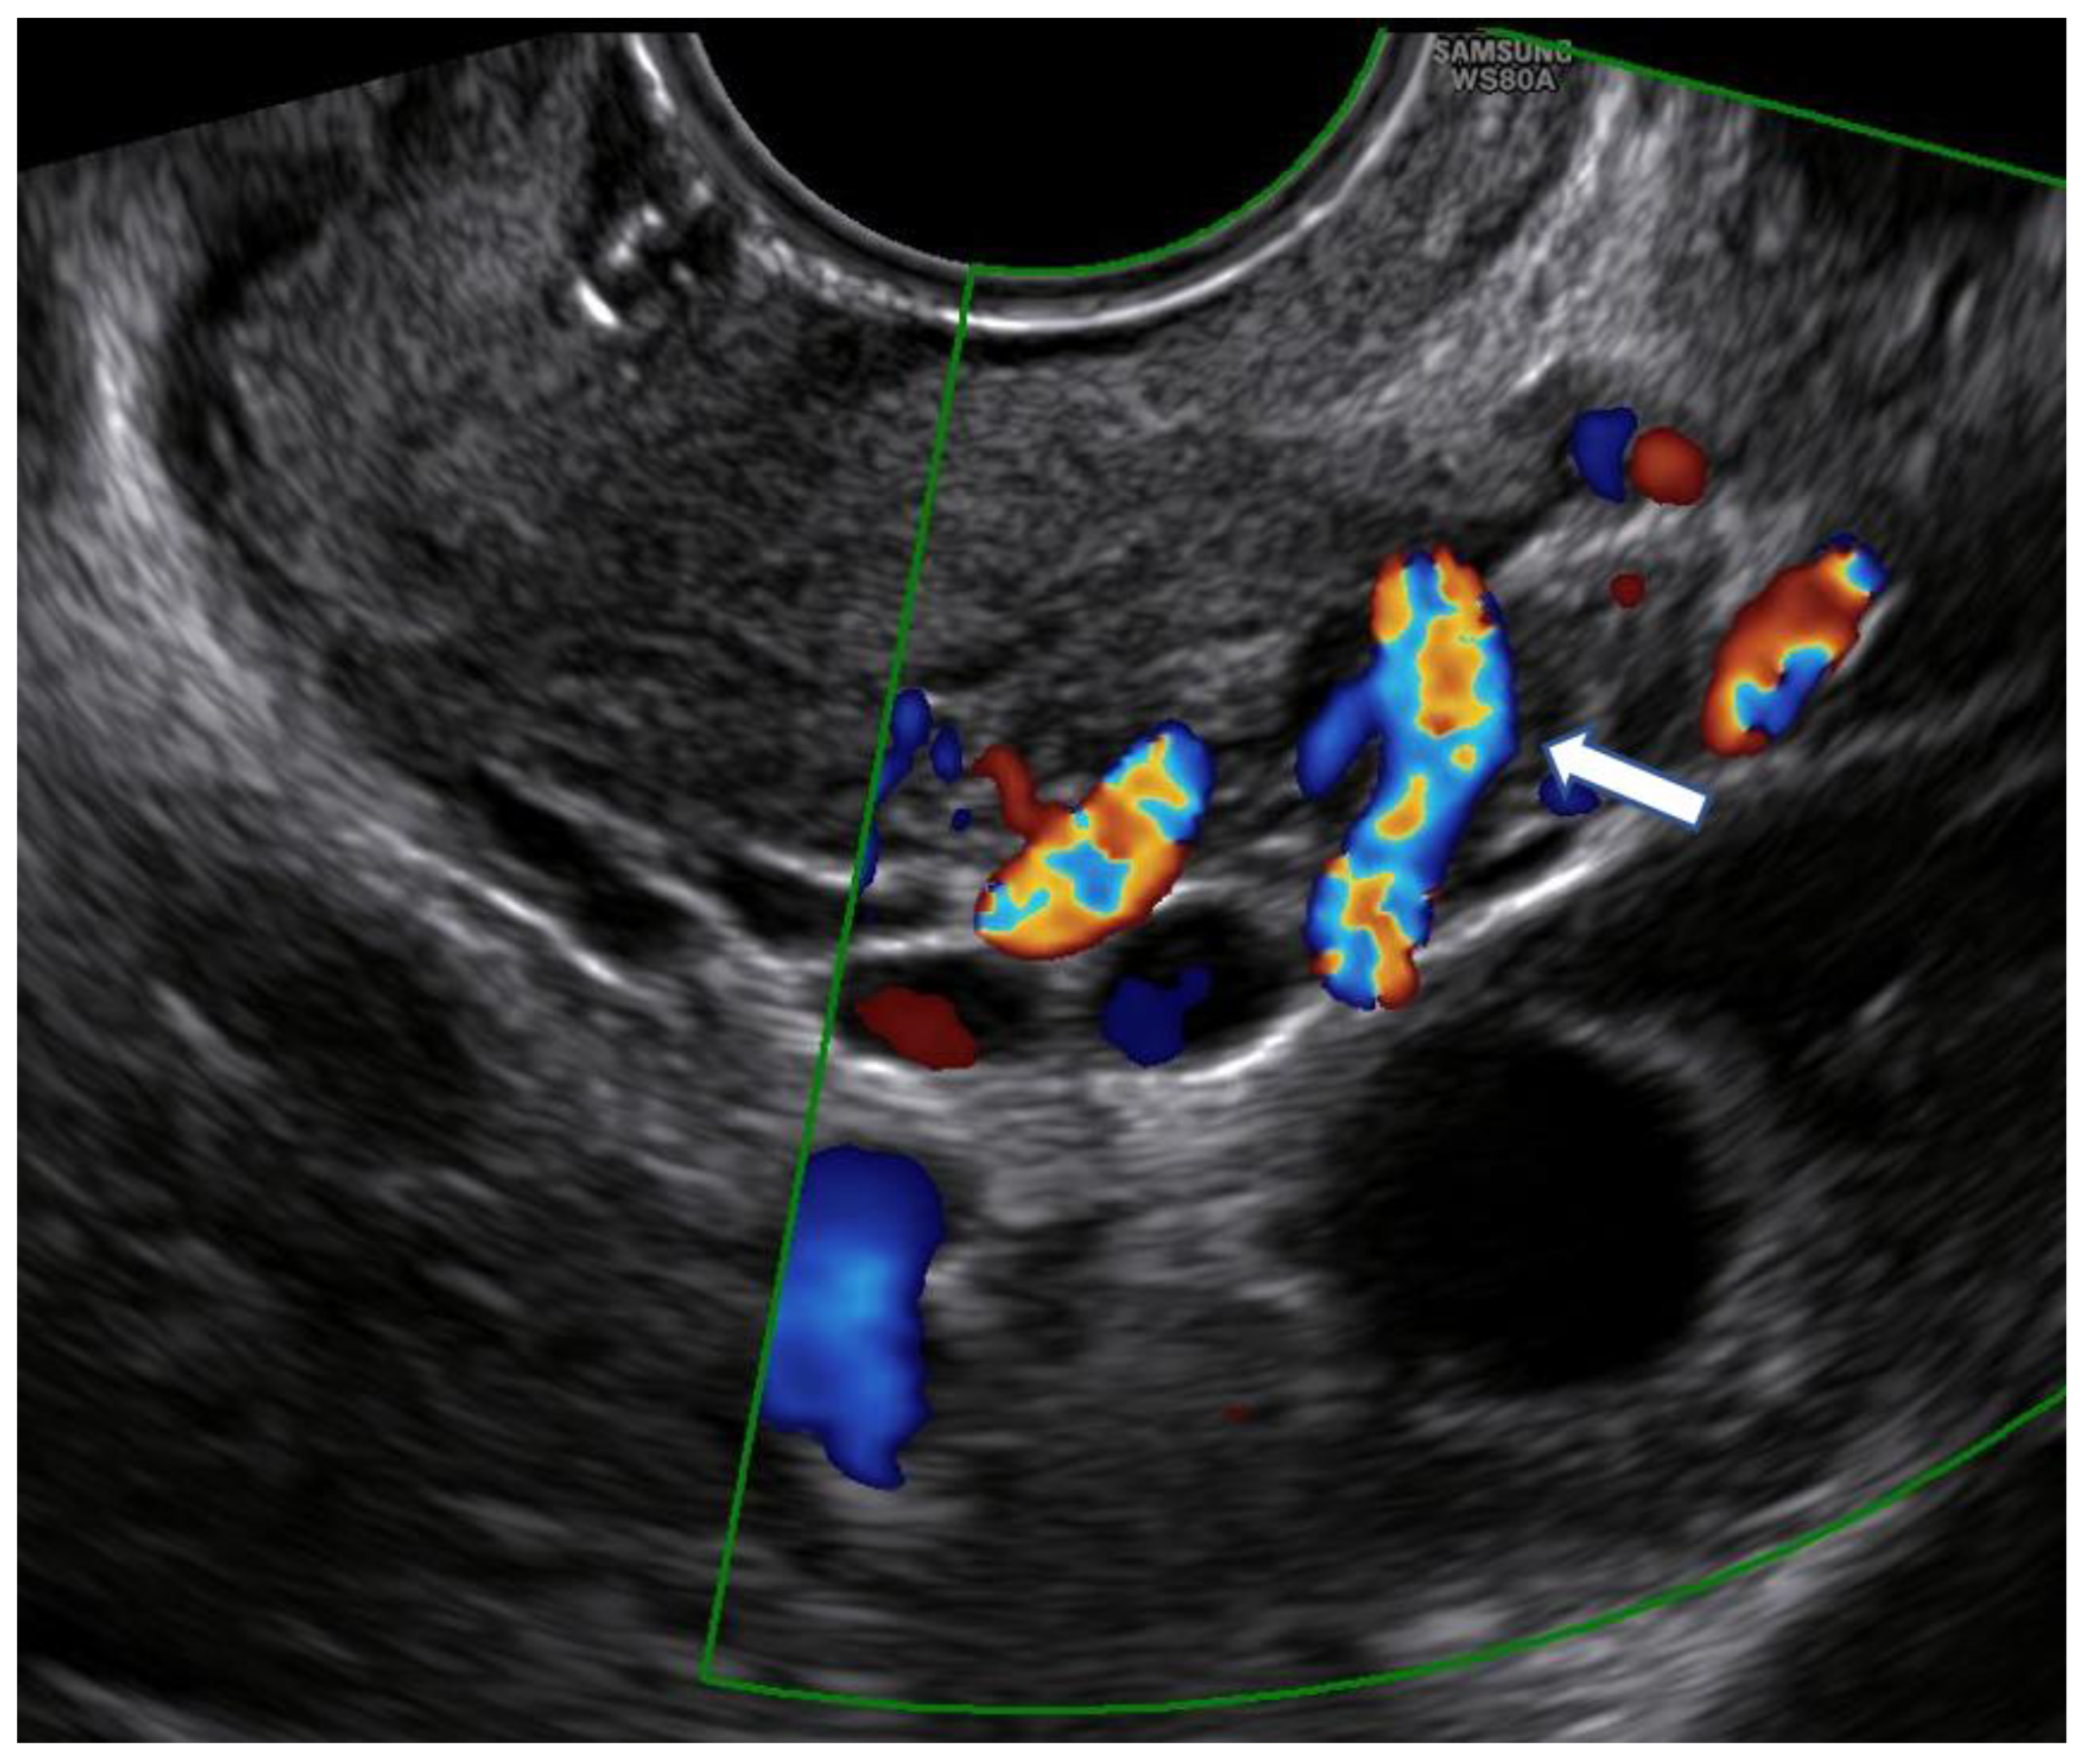

Unlike Kim’s and other previous studies [12,16,21,22], we considered a different upper limit of the cervical canal in our measurements. Because there is no standardized ultrasound procedure to evaluate the cervix in non-pregnant women, internal uterine OS is difficult to detect, and cervicometry may have different ultrasound-dependent measurements. This limit was identified in the line that connects the points where the common trunk of the uterine arteries reaches the uterus splitting into the ascending major branch and the cervical branch. It is clearly visible by ultrasound, with the help of color Doppler (Figure 1).

Figure 1.

Color Doppler use for the identification of the point where the common trunk of the uterine artery reaches the lateral margin of the uterus (arrow).